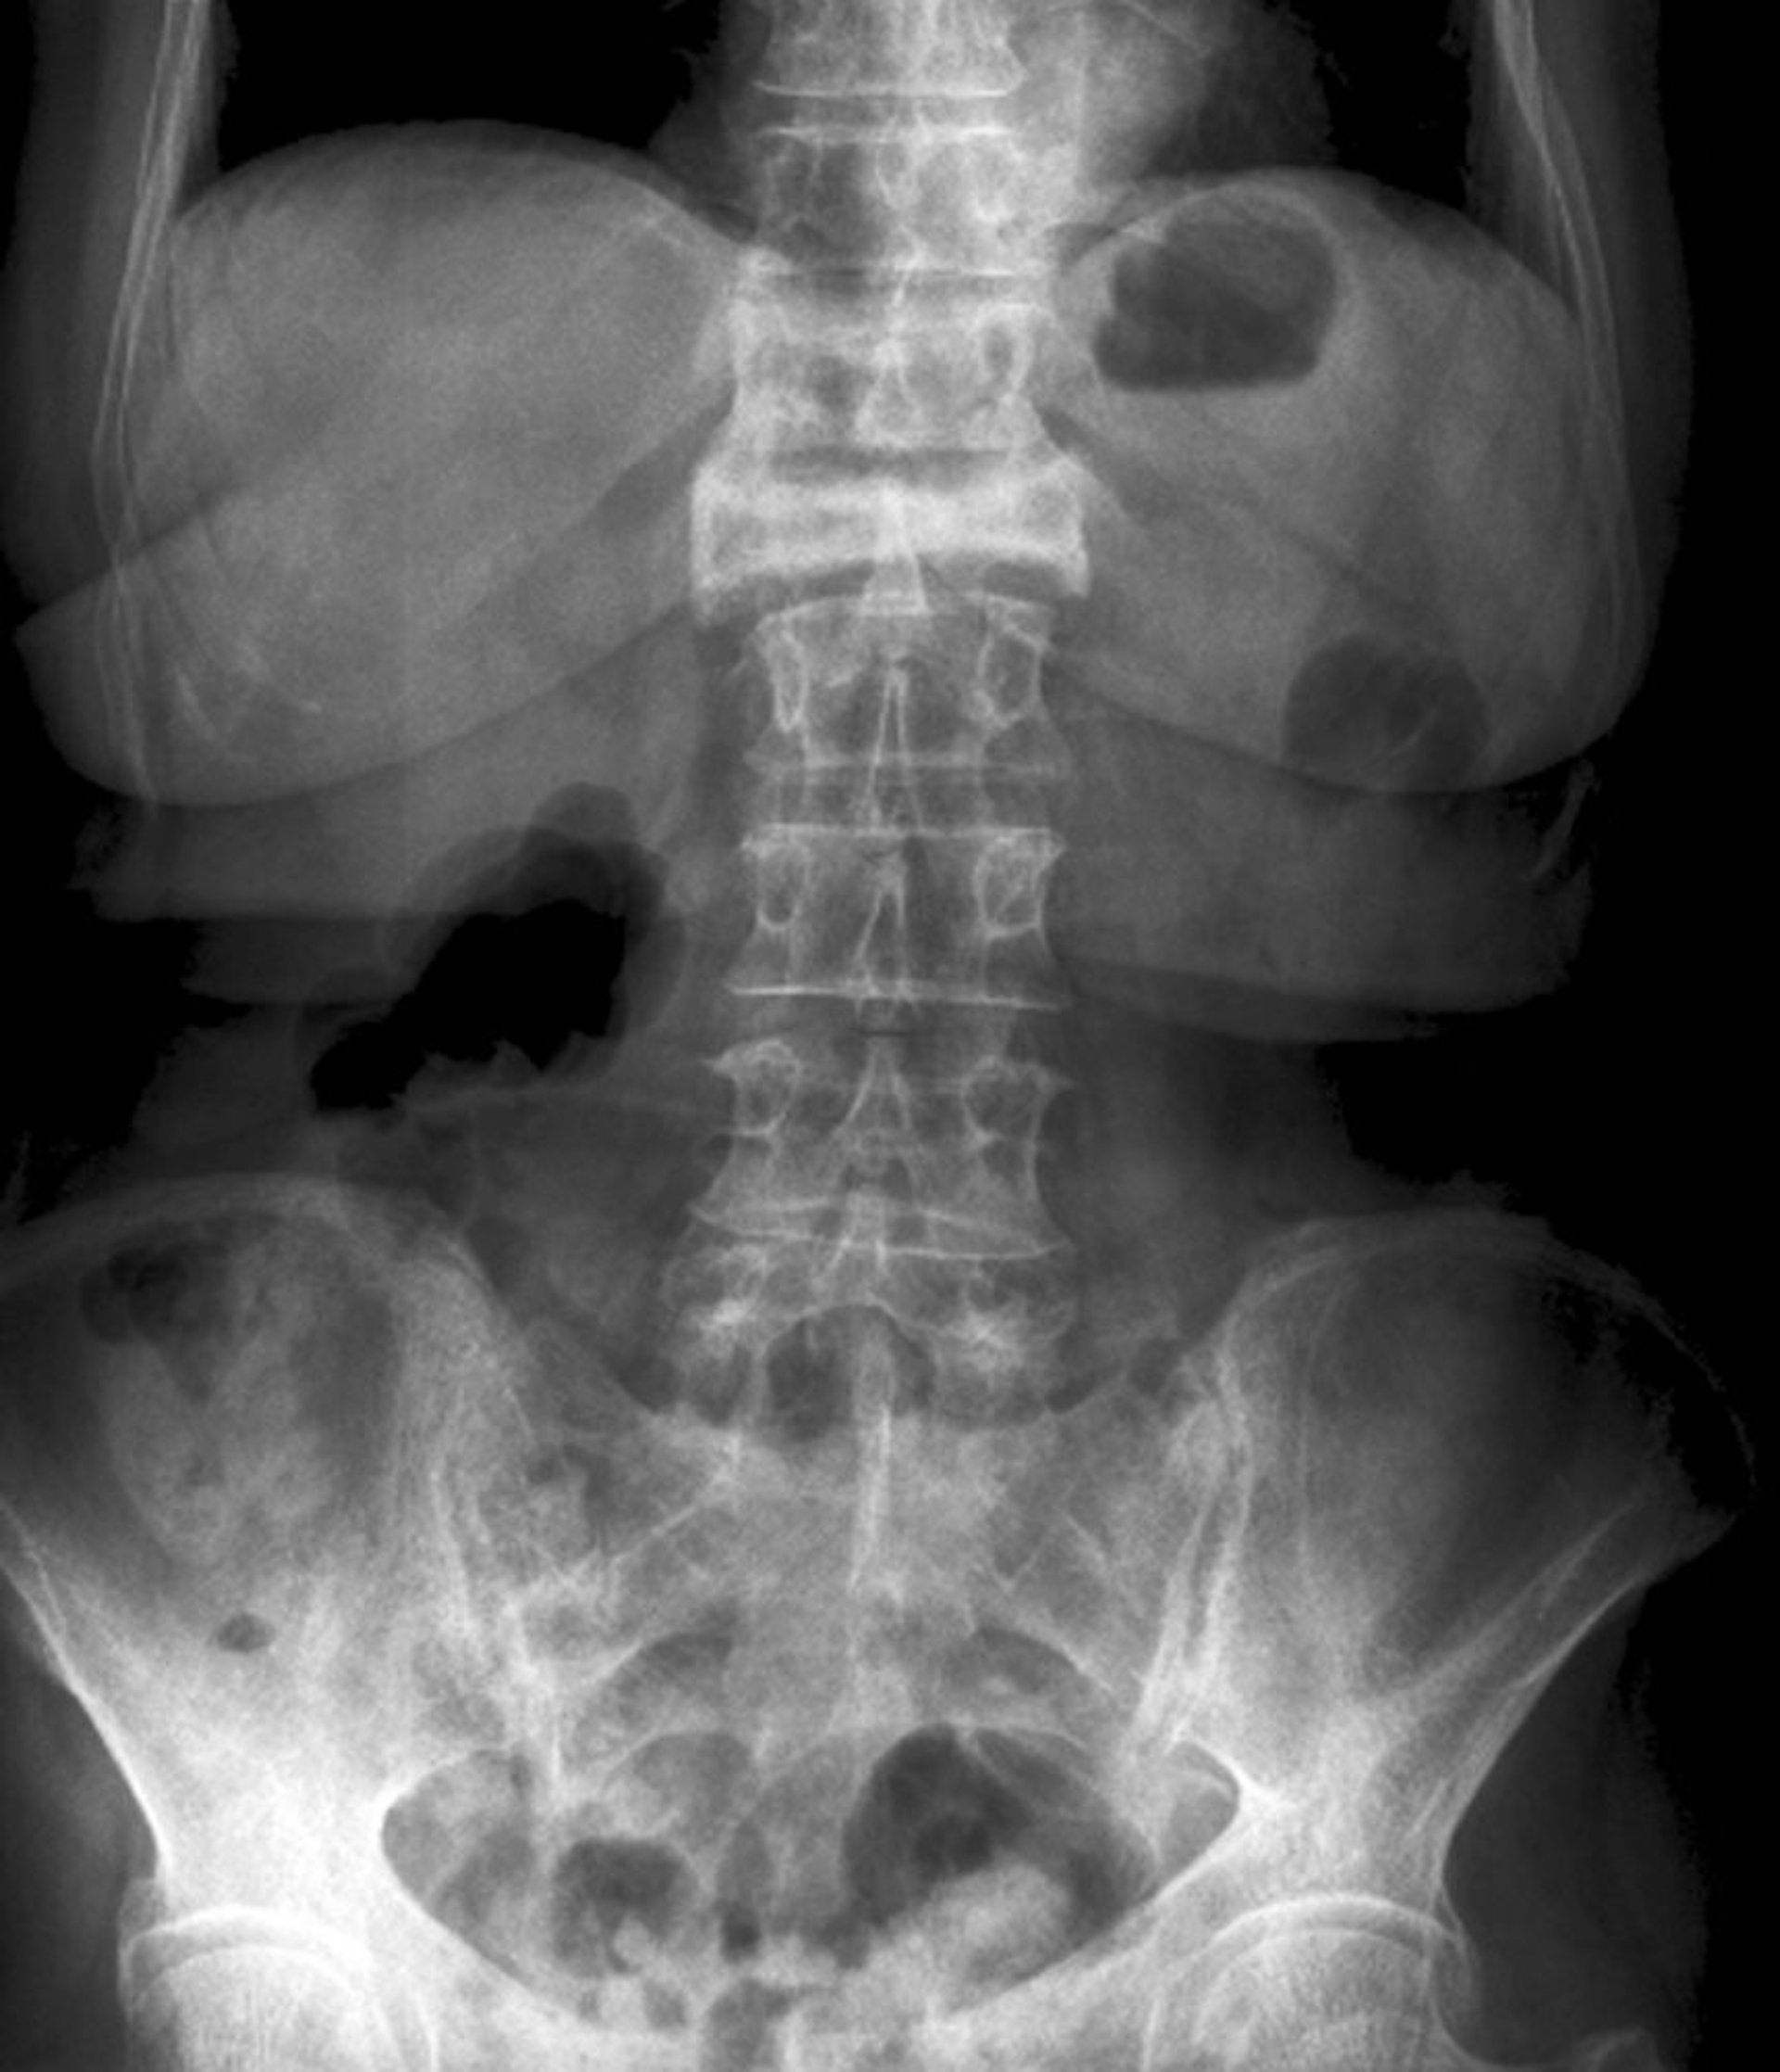

Vista anteroposterior de una fractura por compresión grave

Esta fractura por compresión de la primera vértebra lumbar es visible en la vista anteroposterior como una pérdida importante de altura y un aumento de la radiodensidad.